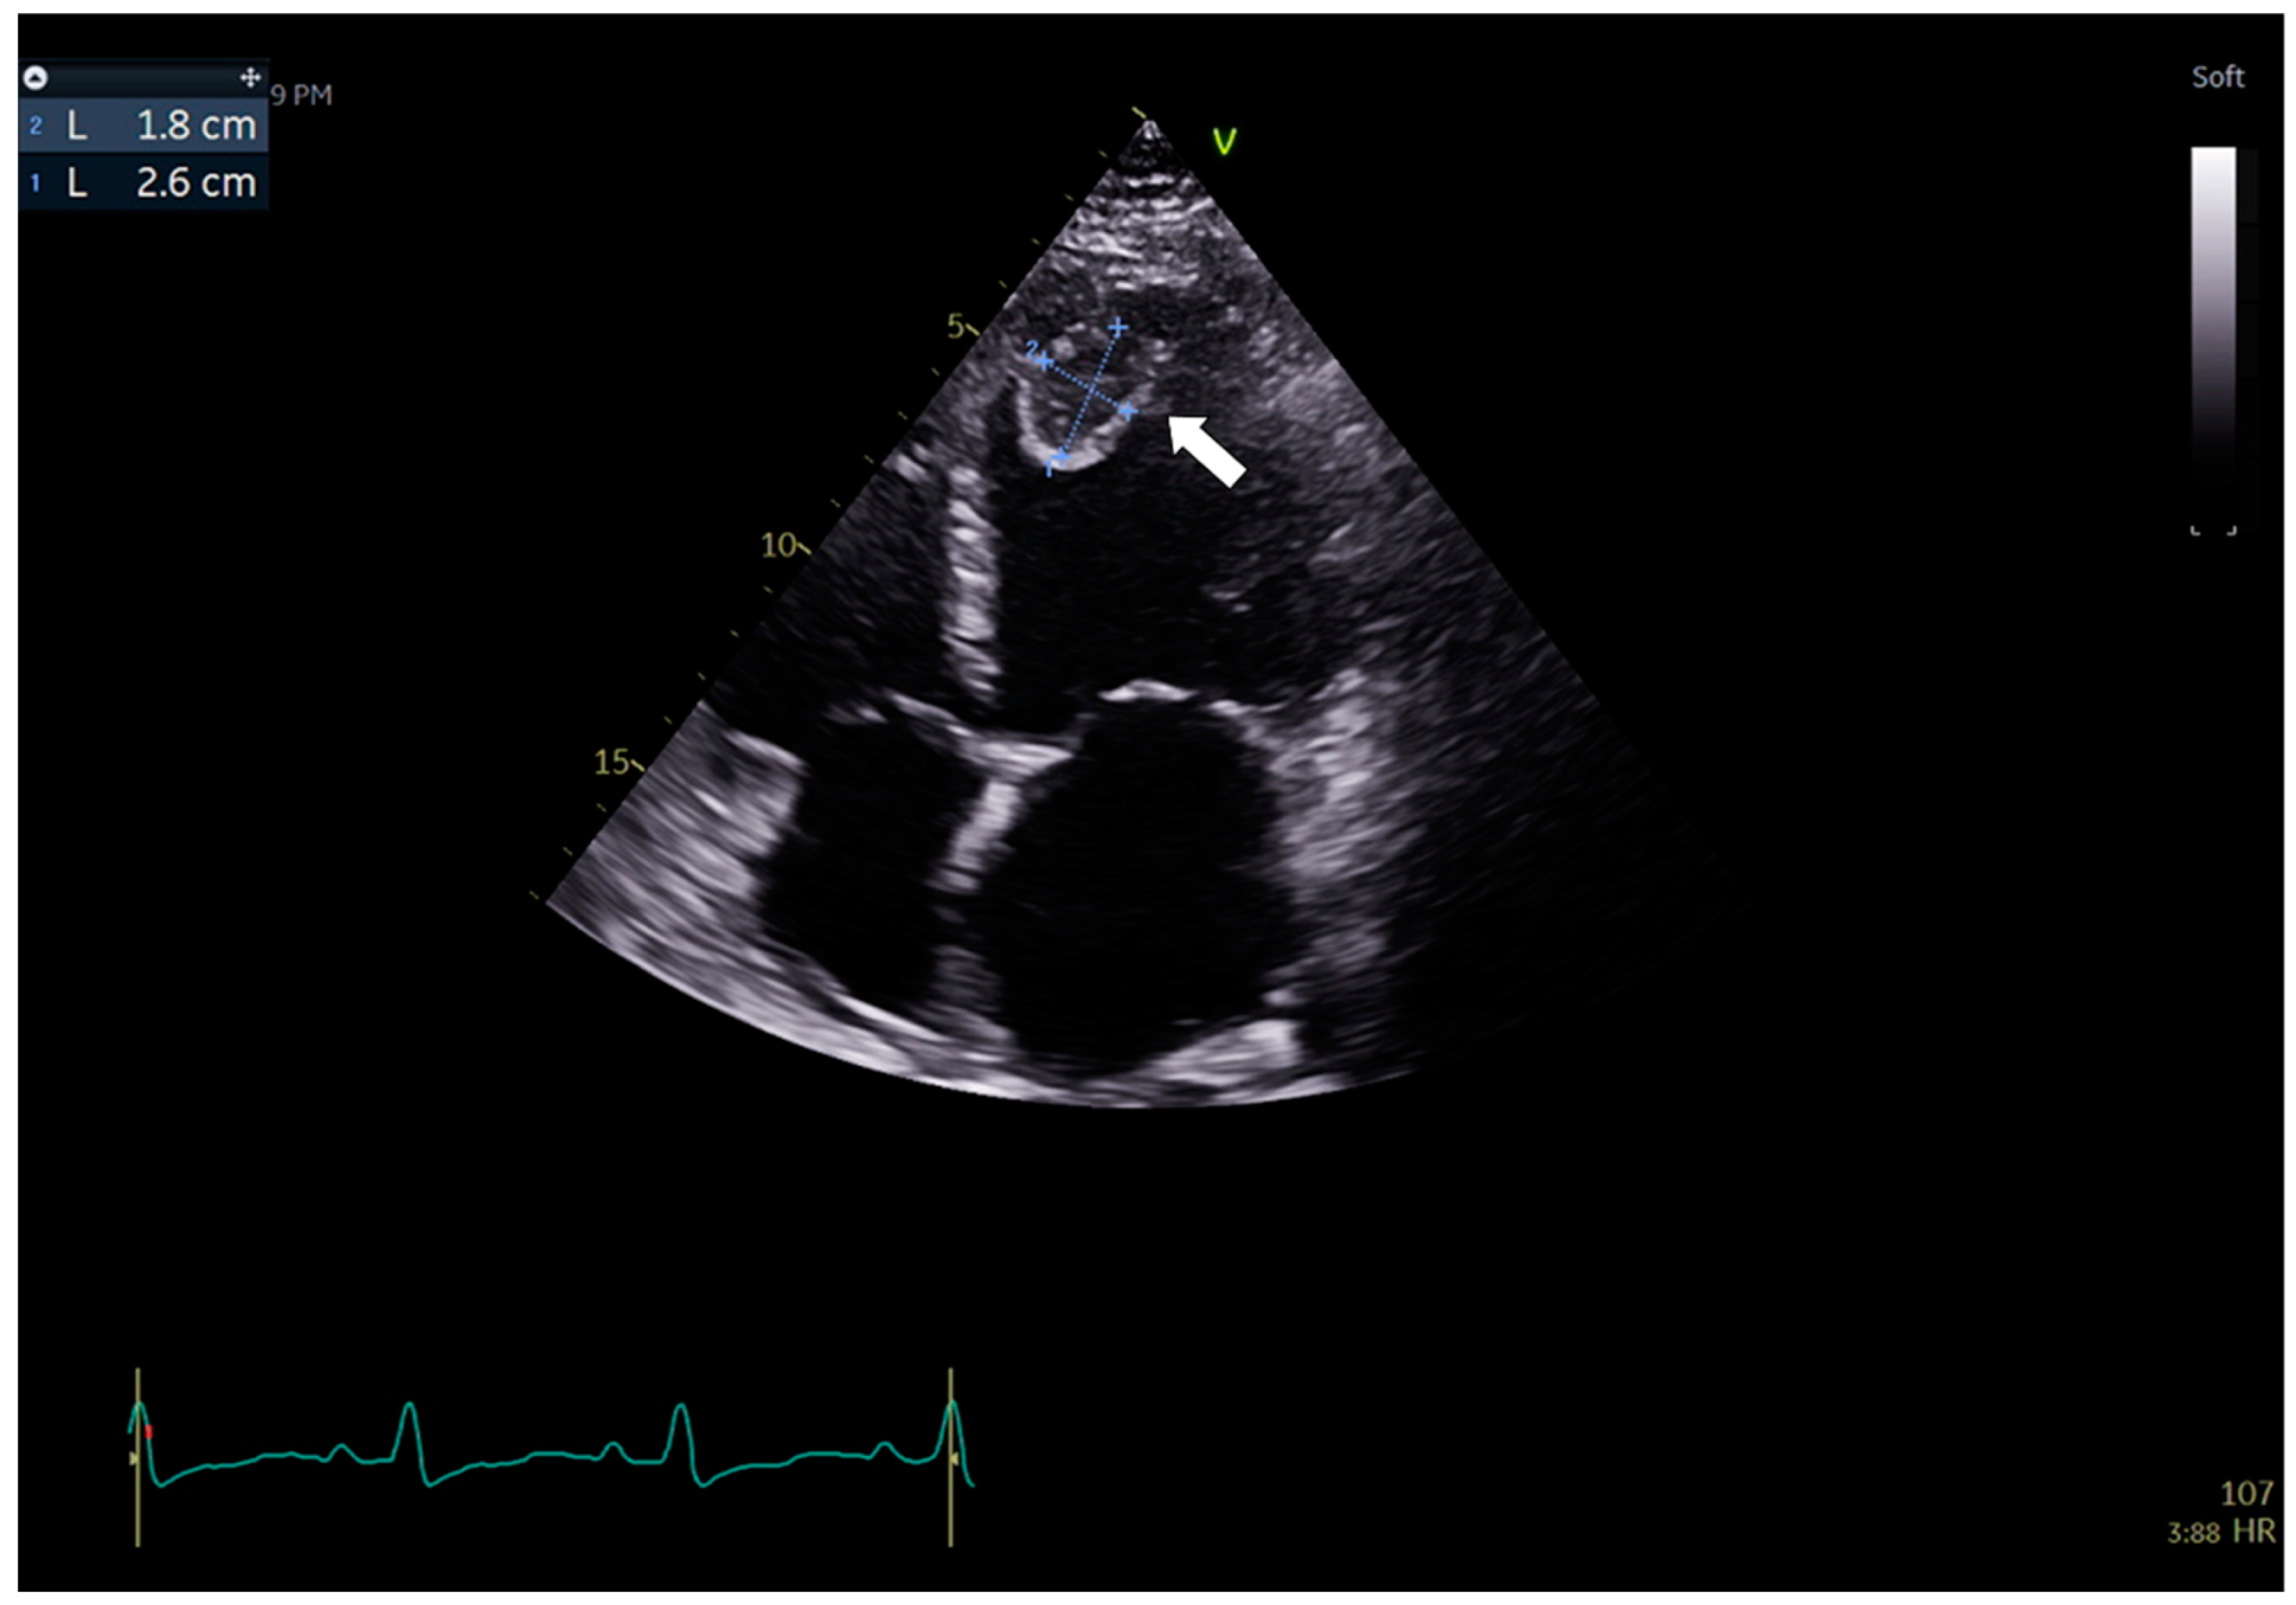

3.1. Case 1

3.2. Case 2

3.3. Case 3